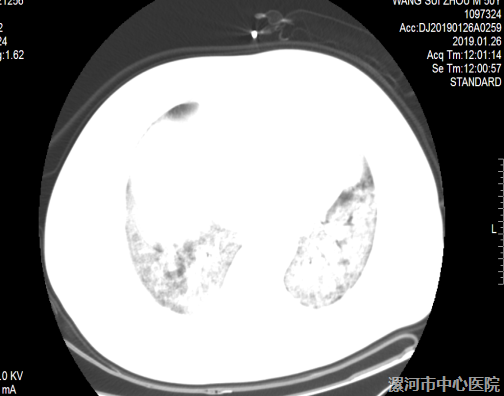

(图1.2为患者入院时肺部CT 2019-01-26)

患者于6日前饮酒后出现发热,最高体温39℃,伴咳嗽、咳黄痰,痰液不易咳出,伴腹泻、稀水样便。患者在当地诊所治疗效果差,遂来我院治疗。门诊以“发热待查”收入全科医学科,给予氧疗效果不佳,遂请我科柳彦涛副主任医师会诊。因患者呼吸急促、口唇发绀、呼吸困难,血氧饱和度难以维持,需急行机械辅助通气,遂转入我科进行抢救性治疗。